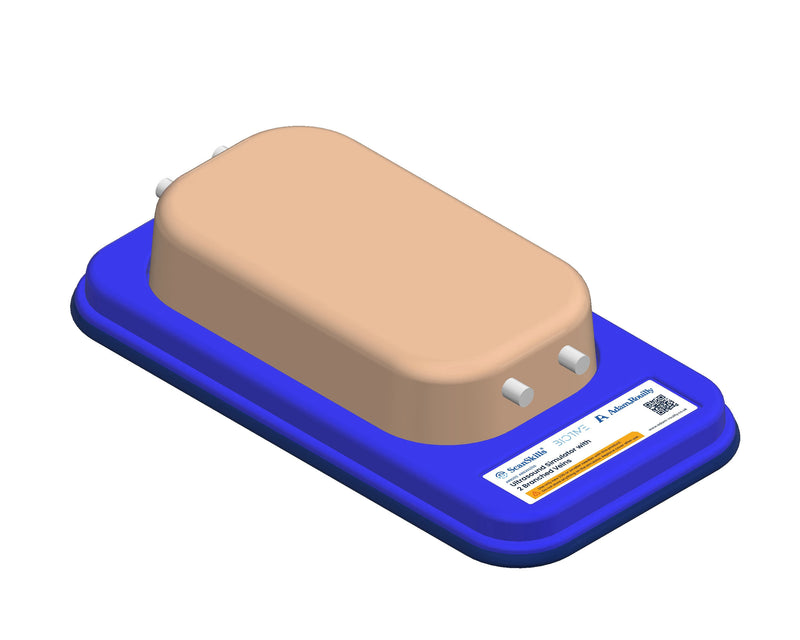

Thiết bị huấn luyện đơn giản, mạnh mẽ cho phép luyện tập lặp đi lặp lại kỹ thuật xâm nhập dưới hướng dẫn siêu âm một cách thực tế, giúp nâng cao thành thạo máy siêu âm, khéo léo sử dụng đầu dò và nhận biết cấu trúc giải phẫu. Tất cả chỉ với việc chuẩn bị và bảo trì tối thiểu.

Máy huấn luyện siêu âm BIOTME® mô phỏng mô người thật cả về cảm giác và đặc tính phản hồi sóng siêu âm. Vết kim sẽ biến mất sau vài ngày luyện tập, tăng cường tính chân thực và tiết kiệm chi phí.

Kích thước (Inch): 13 x 6.7 x 3.15